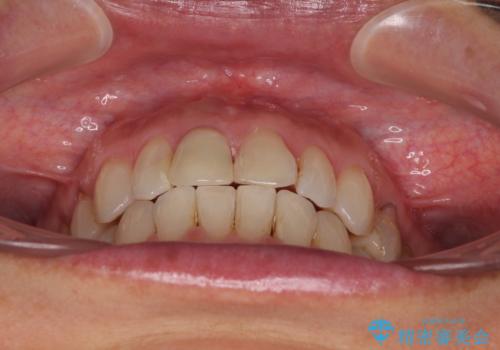

デコボコと銀歯 矯正治療とセラミック治療で綺麗な口元に

- 前歯のデコボコと口を開けたときに見える銀歯を気にして来院された患者様です。

ある程度デコボコが解消されれば大丈夫とのことで、インビザライン・モデレートパッケージを利用して歯列を整えて行くこととしました。

矯正治療後に銀歯をセラミッククラウンなどに置き換えていくと、どうしても後戻りを起こしてしまうため、矯正治療が概ね終了した時点で銀歯を全てセラミックとし、最後に仕上げでインビザラインにを用いて細かいデコボコを改善していくこととしました。

とても明るい口元となり、人目を気にせず、大きく口を開けて笑えるようになりました。